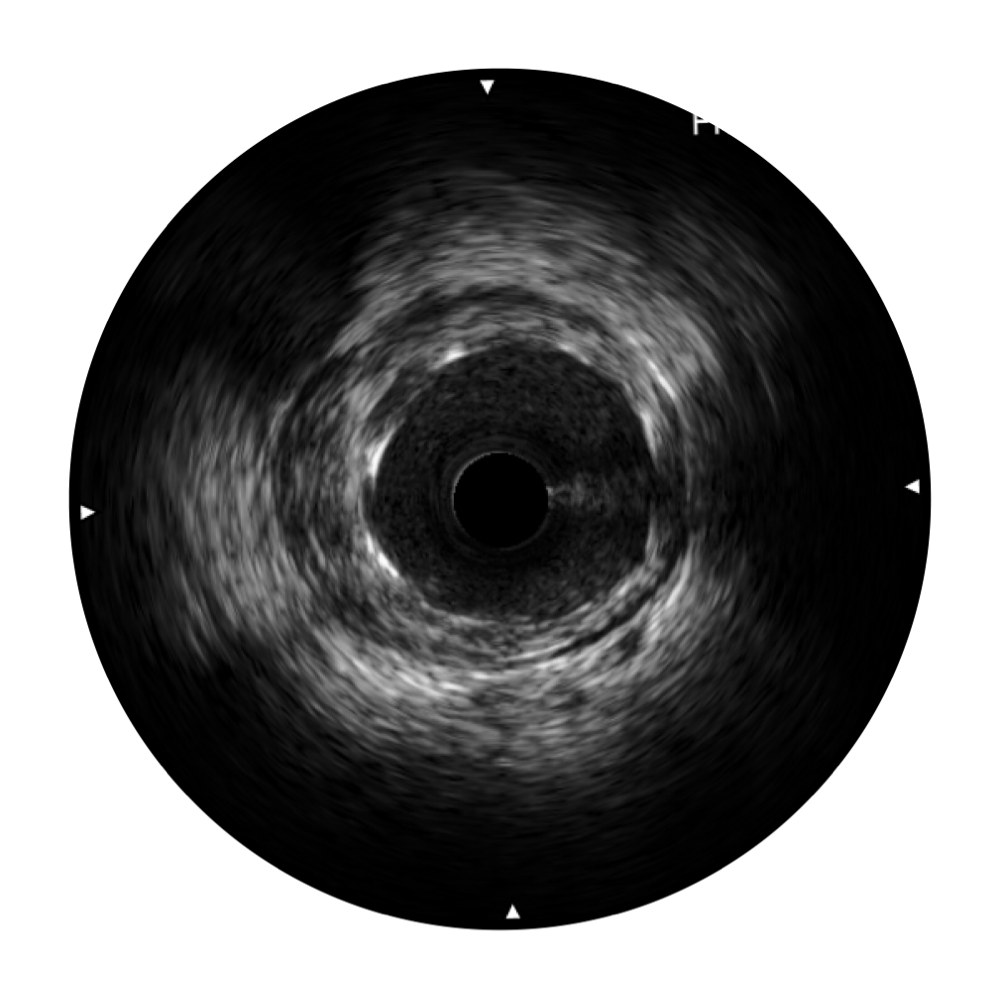

• DB中国旗舰官方网站宽频IVUS图像

对比传统IVUS导管成像,DB中国旗舰官方网站宽频IVUS图像的近场支架梁显影更细腻,远场中膜外血管仍清晰可辨,兼顾远中近,兼顾分辨力与穿透深度